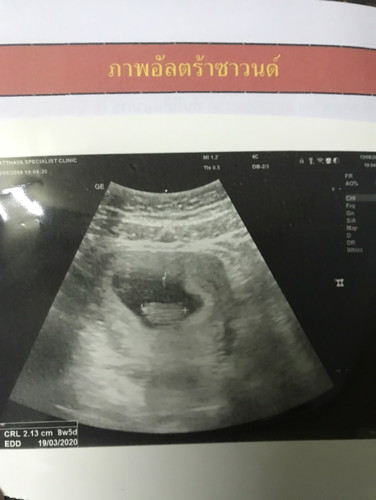

เจอหัวใจลูก

ดีใจมาก8W5D